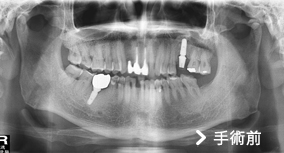

此為埋伏齒手術前後對照照片,照片的左邊其實是病人的右邊。從照片上可以看到左右下牙床智齒成水平狀態,屬於難度高的手術,需開刀拔除。

埋伏齒疼痛度高於其它牙齒問題,有時會造成牙齦會腫,面頰會腫,嘴巴無法張開等問題,一般而言,矯正醫師會在矯正前要求病人拔除埋伏齒,使矯正治療順利進行。

原本矯正好或是原本就很好的齒列,會因為埋伏齒生長,使齒列改變為不齊,影響美觀。大部分病患罹患埋伏齒疼痛,診所醫生都轉診大醫院,原因是:診所設備不足,拔除困難,手術時間長,術後易流血和感染,醫生相對承受風險大。

但轉診的大醫院往往安排數星期才能拔,無法即時解決問題。亞德擁有一流的設備及完善儀器,安排後即可拔牙。免除病人舟車勞頓之苦,且可在術後得到良好的照護。